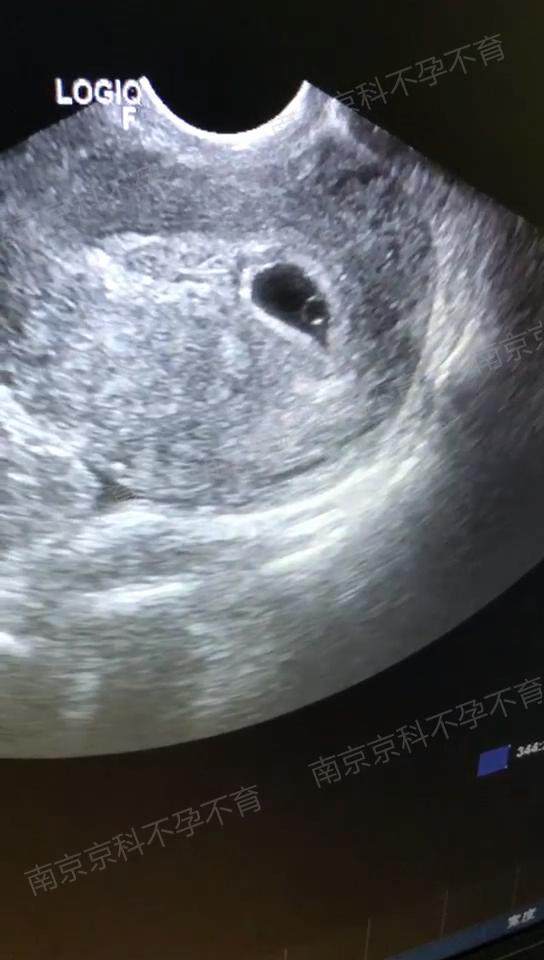

▲B超下检测到胎心胎芽